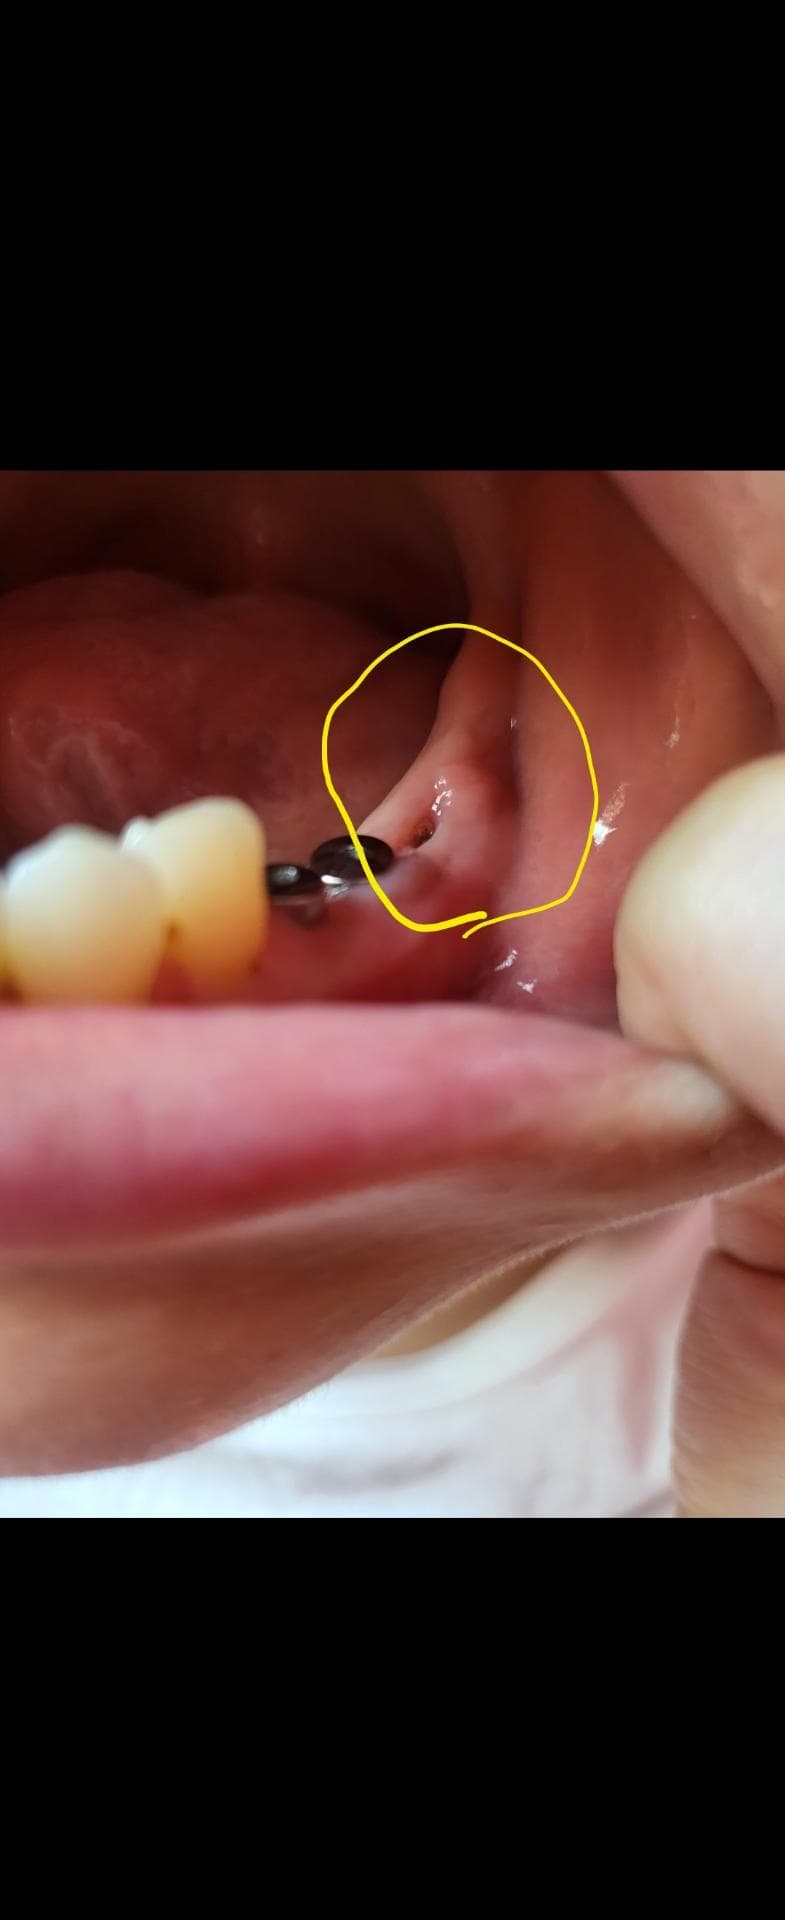

왼쪽 맨 아래 어금니 뼈이식한지 한달되었어요

오늘 이빨닦다가 보니 뼈이식한 주변쪽에 볼록한 느낌이 들어서 염증이 생긴건지 궁금해서 여쭤봅니다 ㅠㅠ

아픈건 하나도 없고 만져도 통증은 없어요

사진에 보이는건 염증이 아니고 잇몸이 눌려서 물집같은게 잡힌거 같습니다. 치과에 가셔서 확인후 터트리거나 그냥 두셔도 될것같습니다.